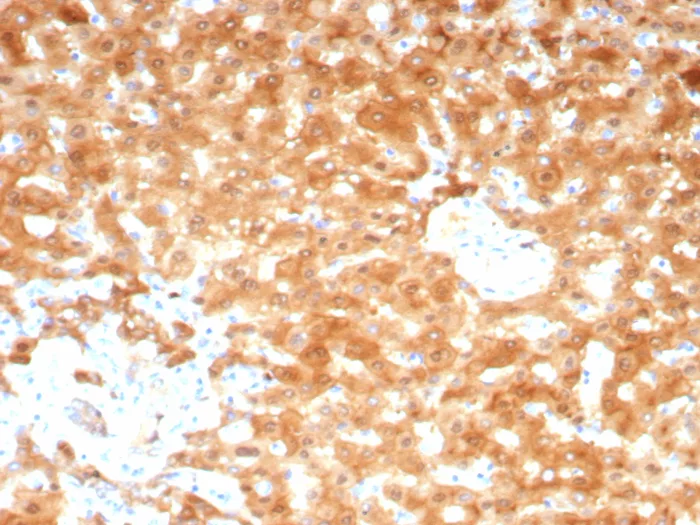

Formalin-fixed, paraffin-embedded human hepatocellular carcinoma stained with AKR1C1 Mouse Monoclonal Antibody (AKR1C1/9070). HIER: Tris/EDTA, pH9.0, 45min. 2°C: HRP-polymer, 30min. DAB, 5min.